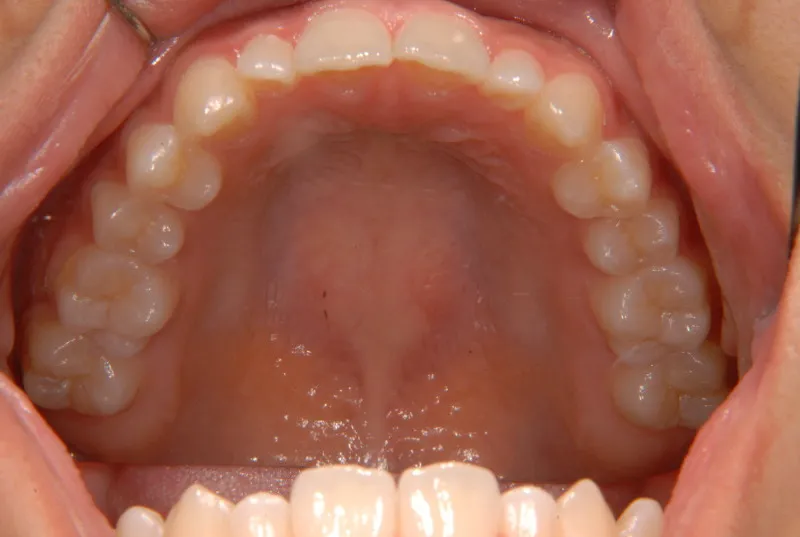

開咬・舌癖・18歳女性

初診時年齢 高校生 (女性) 主訴 開咬 舌癖

状態 前歯で噛めない(開咬/オープンバイト)